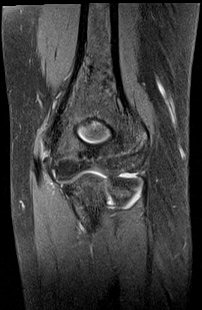

ÀÚ±â°ø¸í°Ë»ç

ÆÈ²ÞÄ¡ ̫̿ ÃøºÎÀÎ´ë ÆÄ¿­ ¹× °ß¿­°ñÀý(±×¸² 8, 9)